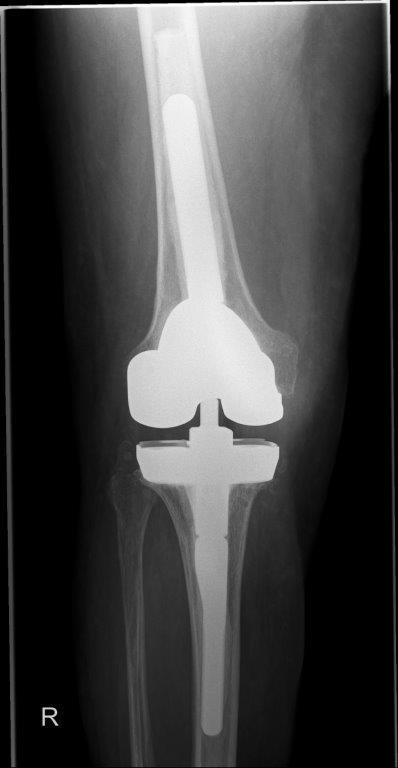

Radiologisches Ergebnis nach mehrfachem Wechsel Knie TEP